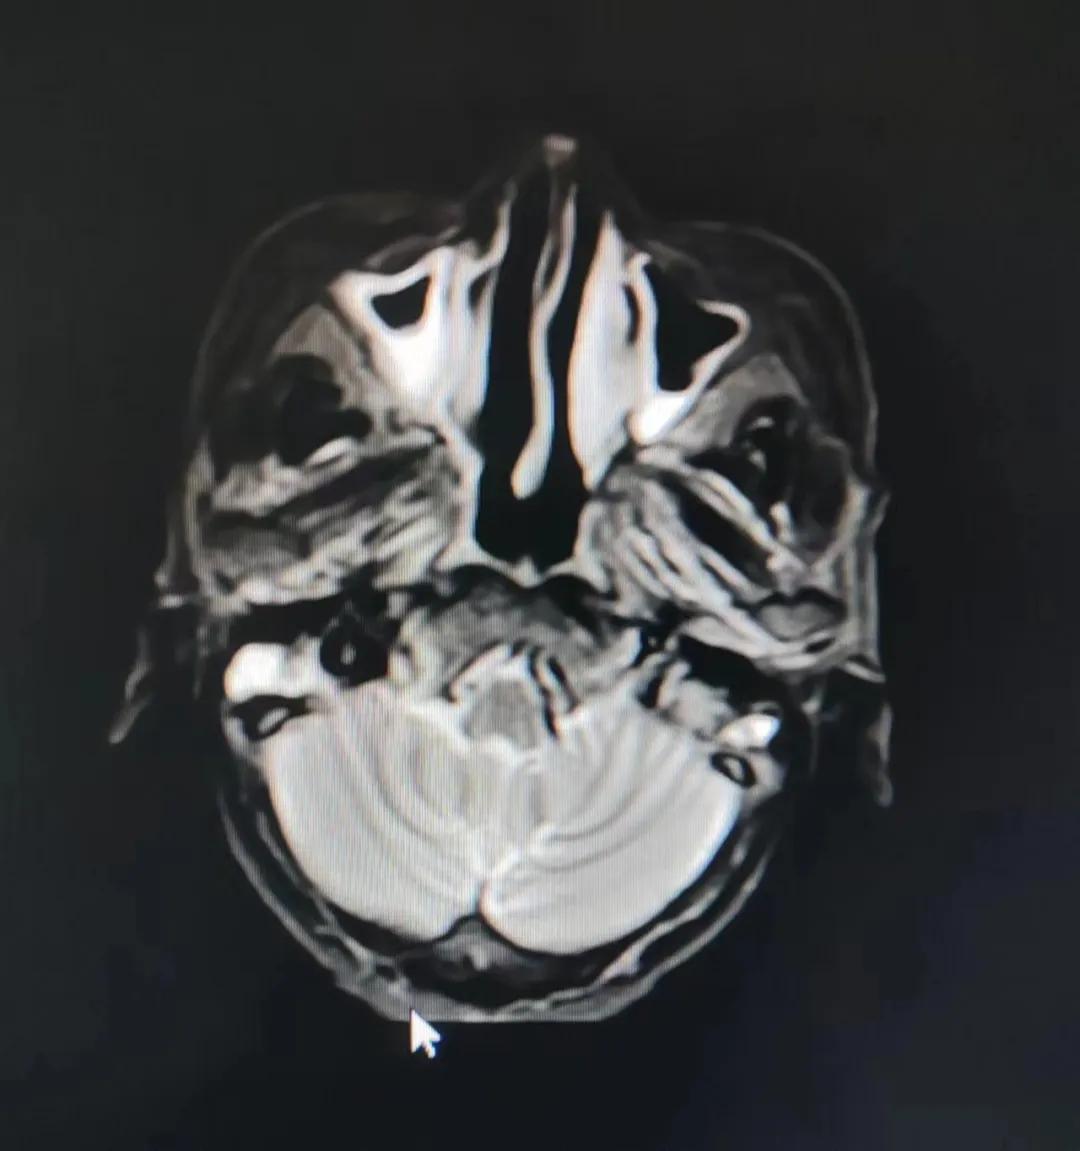

治療前

老人因鼻部腫物堵塞鼻腔并且侵犯鼻咽導(dǎo)致鼻塞、疼痛、吞咽困難,身心都備受煎熬,趙亮主任在詢問(wèn)其病史期間幾度落淚。趙亮主任向患者及家屬解釋說(shuō):“現(xiàn)代放療比過(guò)去的傳統(tǒng)放療設(shè)備先進(jìn),技術(shù)不斷提升,能對(duì)腫瘤區(qū)域的照射劑量進(jìn)行優(yōu)化,做到準(zhǔn)確定位、精準(zhǔn)照射,同時(shí),最大限度地降低正常組織的受量,對(duì)全身情況影響很小。”

考慮到患者年齡較大、體質(zhì)差,手術(shù)難度大,且常規(guī)的放射治療難以保護(hù)患者晶體造成患者雙眼視力損傷,放療團(tuán)隊(duì)以最快的速度制定了精準(zhǔn)放射治療方案并開(kāi)始為其實(shí)施治療。僅僅數(shù)日后,老人腫塊出血即得到控制,腫塊明顯縮小,放療20次后腫塊迅速縮?。?/div>